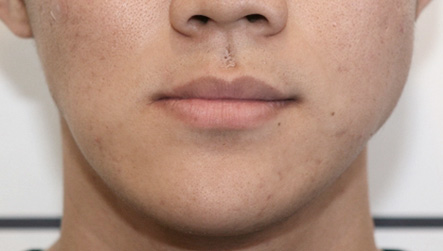

"교정이 끝나면 무엇부터 하고 싶으세요?"

당신은 sns에 셀카를 잔뜩 올립니다.

남이 찍어주는 사진에도 당당할 수 있습니다.외모 콤플렉스가 사라지니 일 처리도 빨라집니다. 그래서 승진도 하고, 원하던 이성과 연예도 시작합니다.

하루하루 행복해 이래도 되나 싶을 겁니다.

이것은 남의 일이 아닙니다. 얼굴 비대칭 교정 후 당신 일입니다.

이제 본격적으로 시작하는 일만 남았습니다. 나이가 어릴수록 교정 효과가 좋습니다.

당신에게 행복을 선물하세요.비수술 턱 교정이면 당신의 고민 탈출이 가능합니다.